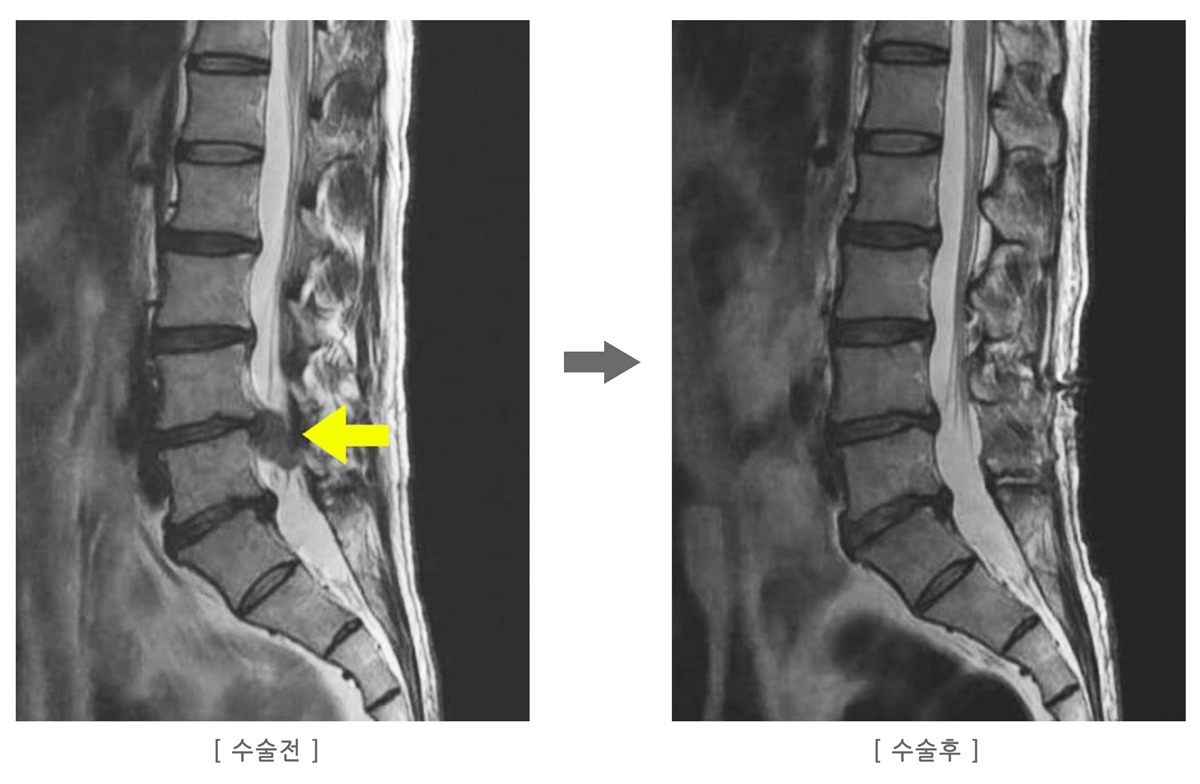

MRI 결과: “디스크가 다시 터졌습니다”

MRI를 본 의사 선생님은 말했습니다.

“디스크가 재파열됐습니다. 일단 입원하여 물리치료, 도수치료, 주사로 통증을 다스려보고 안되면 재수술을 합시다.”